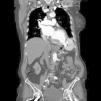

At six-month follow-up, the patient remains asymptomatic, with no adverse events, and the device is in the appropriate position confirmed by CT (Figures 3 and 4).

Figure 3.

Computed tomography angiography (coronal view) showing the Amplatzer® ASD device six months after the procedure.